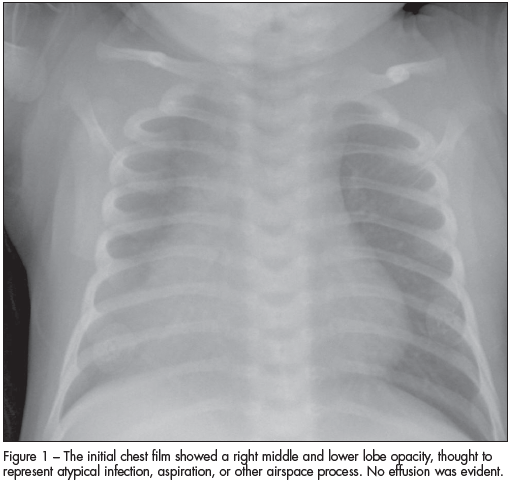

Staphylococcal Pneumonia

Gurpreet Vidwan, MD

Patients with staphylococcal pneumonia frequently have an associated pleural effusion or pneumothorax.